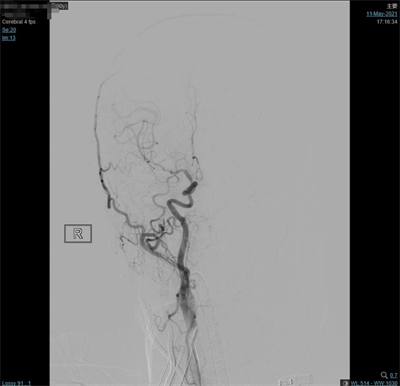

夹闭后造影

患者气管插管全麻满意后,双侧腹股沟区常规消毒铺巾,右侧腹股沟韧带下方股动脉搏动最强点下方约1.5cm处穿刺,右股动脉行Seldinger穿刺,置入5F动脉鞘,超滑泥鳅导丝携带5F单弯造影管分别行双侧颈总动脉、双侧颈外动脉及双侧椎动脉正侧位造影,造影见:右侧大脑中动脉M1分叉处2个动脉瘤;左侧大脑中动脉M1分叉处2个动脉瘤,其中一个可见子瘤。仰卧位头右偏。常规碘酒及酒精消毒后铺巾。取左额颞弧形切口,逐层切开头皮及皮下,切开颞肌筋膜及颞肌,筋膜下入路,颞肌翻向下方,暴露颅骨。颅骨钻1孔,铣刀铣下骨瓣约5X3cm大小。硬膜张力不高。分离蝶骨嵴两侧硬脑膜,进一步咬除蝶骨嵴。硬膜四周悬吊。弧形剪开硬脑膜,向前翻转固定。显微镜下锐性分离侧裂,打开蛛网膜,放出脑脊液后脑组织压力下降,显露颈内动脉,大脑中动脉及其分支,见动脉瘤位于大脑中动脉M1段。分离动脉瘤两侧粘连蛛网膜,显露动脉瘤前后端中动脉及其分支,分离瘤蒂两侧,上1枚临时阻断夹阻断左侧大脑中动脉,后更换另1枚临时阻断夹阻断左侧大脑中动脉,上3枚德国进口动脉瘤夹夹闭2个动脉瘤瘤蒂,调整后夹闭满意,松阻断夹,术中动脉瘤未破裂。造影显示中动脉及其分支通畅。创面止血,覆盖止血纤维及凝血酶海绵,生理盐水冲洗清亮,脑组织搏动良好。护士清点棉条、棉片、纱布及器械无误,严密缝合硬膜。骨瓣复位,3枚钛片固定。逐层缝合颞肌、颞肌筋膜、皮下及头皮各层。包扎固定纱布,酒精消毒术前贴膜,将患者头左偏,取右额颞弧形切口,逐层切开头皮及皮下,切开颞肌筋膜及颞肌,筋膜下入路,颞肌翻向下方,暴露颅骨。颅骨钻2孔,铣刀铣下骨瓣约5X5cm大小。硬膜张力不高。分离蝶骨嵴两侧硬脑膜,进一步咬除蝶骨嵴。硬膜四周悬吊。弧形剪开硬脑膜,向前翻转固定。显微镜下锐性分离侧裂,打开蛛网膜,放出脑脊液后脑组织压力下降,显露大脑中动脉及其分支,见动脉瘤位于大脑中动脉M1段,分离动脉瘤两侧粘连蛛网膜,显露动脉瘤前后端中动脉及其分支,分离瘤蒂两侧,第3枚临时阻断夹阻断右侧大脑中动脉上一枚德国进口动脉瘤夹夹闭瘤蒂,调试后夹闭满意,松阻断夹,术中动脉瘤未破裂。造影显示中动脉及其分支通畅。创面止血,覆盖止血纤维及凝血酶海绵,生理盐水冲洗清亮,脑组织搏动良好。护士清点棉条、棉片、纱布及器械无误,严密缝合硬膜。骨瓣复位,3枚钛片固定。逐层缝合颞肌、颞肌筋膜、皮下及头皮各层。手术顺利,术中出血约700ml,回输自体血140ml。手术时间较长,患者带气管插管安返神经外科-ICU病房。